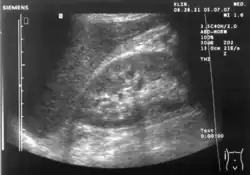

Ultrasound of liver (left side of the image) and right kidney (right side of the image) and Morison's pouch, not containing fluid

Ultrasound of liver (left side of the image) and right kidney (right side of the image) and Morison's pouch, not containing fluid -